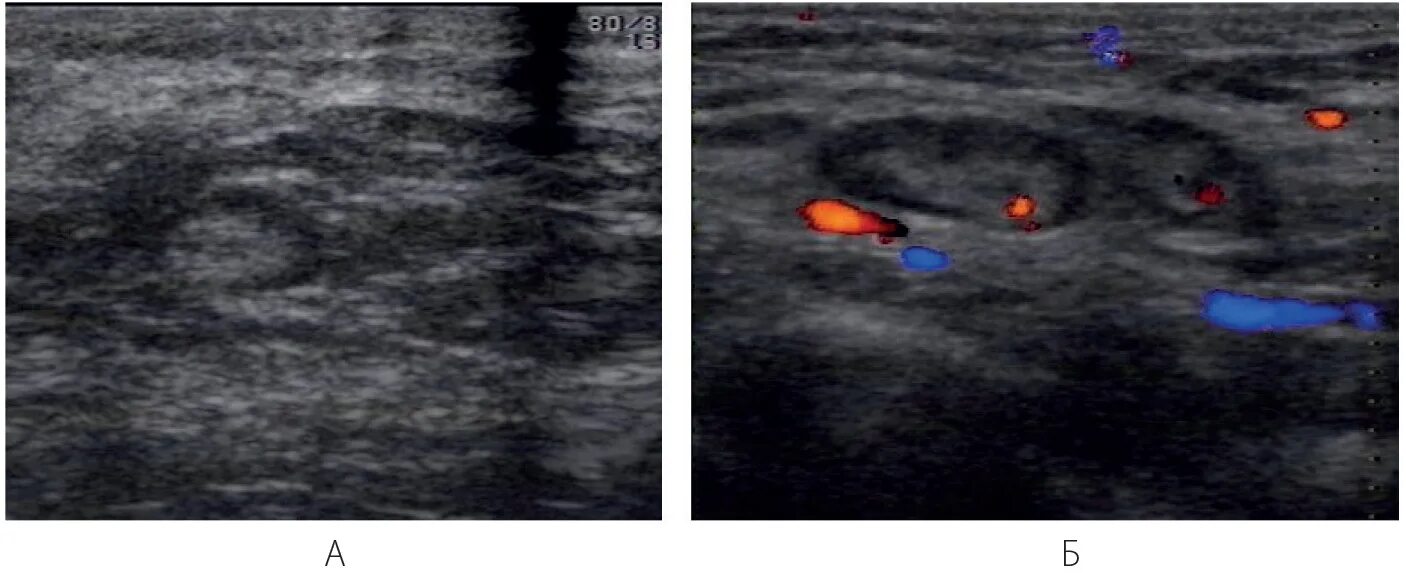

Узи молочных киров